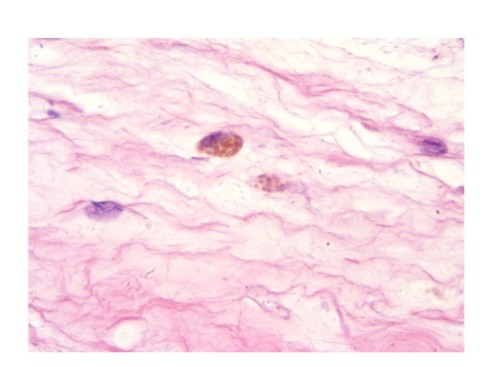

The pathologist usually tries to estimate the duration of meconium exposure in the amniotic cavity on the depth of pigment macrophages in the membranes. The concept is that bile pigment in the meconium is transported across the amnion and that as it diffuses macrophages will ingest it at progressively deeper levels, basically amnion then chorion (Fig 2). In some fetal membranes meconium can be seen on the surface of the amnion or staining the surface epithelium without pigment in macrophages. In others, pigment macrophages are in the amnion connective tissue or the chorion connective tissue or the decidua. This concept was tested experimentally by applying meconium at different concentrations (5-20%) to pieces of placenta in culture21. This was hardly physiologic but has served as a useful estimate for pathologists. The study found no effect of meconium concentration, but that seems unlikely from experience, and the threshold for recognizing the pigment under the microscope may vary among individuals, but they found that it took approximately 2 hours to see pigment in the amnion connective tissue and 3 hours in the chorion connective tissue. They did not have decidua beneath the membranes nor umbilical cord, and therefore could not comment on duration of pigment macrophages in those locations.

Fig 2: The pigmented macrophage in the center is within the chorion connective tissue of the fetal membranes. The pigment is in granules suggestive of accumulation in lysosomal granules. This may be of longer duration than pigment that diffusely stains the macrophage cytoplasm. (H&E, 100X)